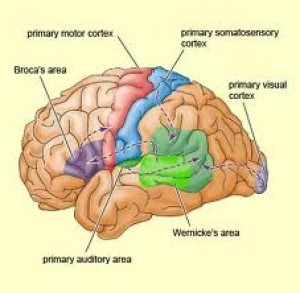

Seperti yg dikatakan tim dokterku di San San Fransisco, area perdarahan ku adalah di pariental lobe, yg mana :

1.1. Primary and secondary somatosensory.

2.2. Postcentral and supramarginal gyrus.

3.3. Angular gyrus.

Gambar sebelah kiri adalah otak kiri, karena pariental lobe ada juga di sebelah kana otak kanan. Gambar di sebelah kanan, adalah pembagian area yg terkenasensorik utama ( primary somatosensory ).